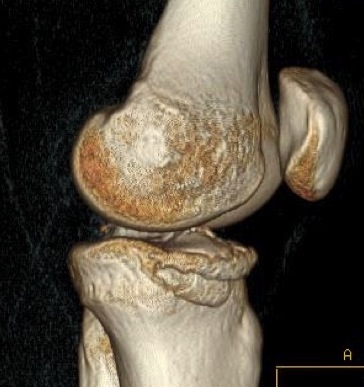

Fibula head avulsion / dislocation

Will typically have LCL and biceps femoris ligament attached

Fibular head avulsion

Fibula head avulsion and medial tibial plateau fracture